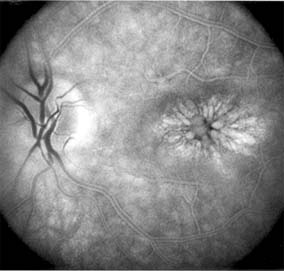

Central serous chorioretinopathy is characterized by serous detachment of the sensory retina as a consequence of focal leakage of fluid from the choriocapillaris through a defect in the retinal pigment epithelium (Figures 10-2 and 10-3). This disease typically affects young to middle-aged men and may be related to life stress events. Most patients present with the sudden onset of blurred vision, micropsia, metamorphopsia, and central scotoma. Visual acuity is often only moderately decreased and may be improved to near-normal with a small hyperopic correction.

Figure 10-2

Figure 10-2: Central serous chorioretinopathy with sensory retinal detachment (arrows) extending into the fovea.

Figure 10-3

Figure 10-3: Fluorescein angiogram of central serous chorioretinopathy shows active disease with both a retinal pigment epithelial detachment (small arrows) and a sensory retinal detachment (large arrows). Two foci of inactive disease (open arrows) are also present.